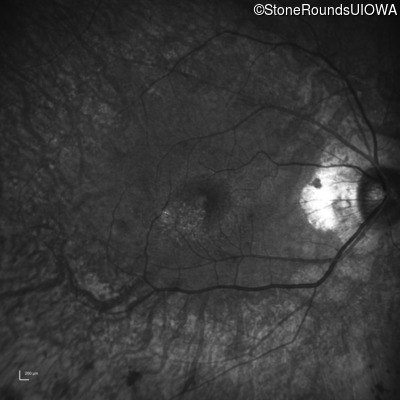

Visit at age: 59 years

Infrared Fundus Photograph - Right - 20/20 -1

Exemplar